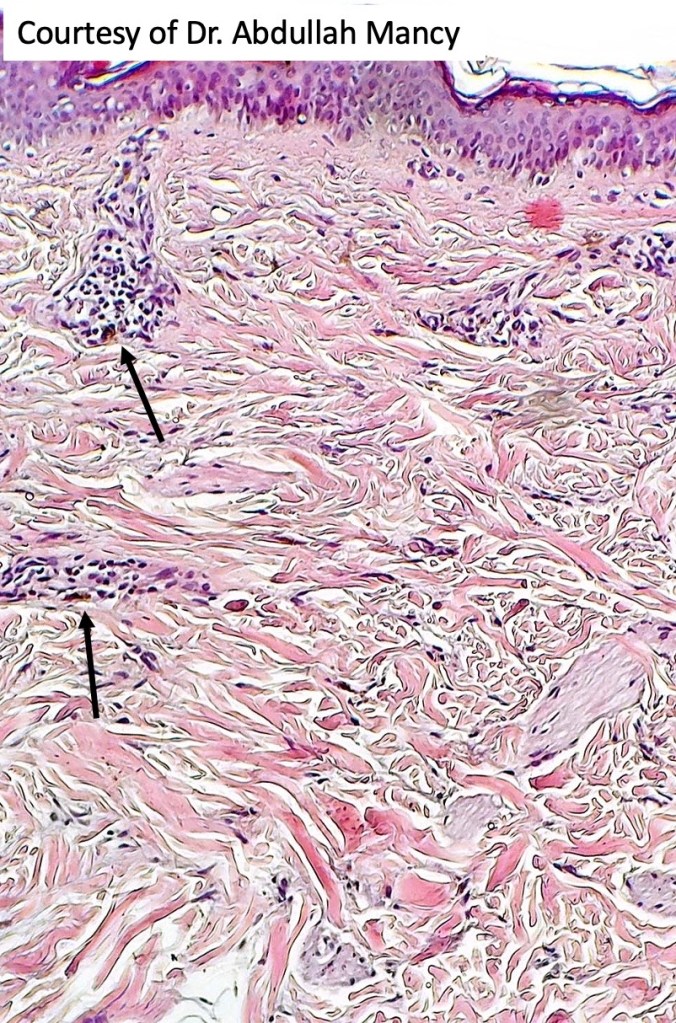

Histologically the features are very subtle and may require a Masson Fontanna stain or immunohistochemistry for diagnosis. Small numbers of dendritic melanocytes are present in the deep dermis siad to be orientated parallel to the epidermis.

Histologically, both lesions are characterized by the presence of denritic melanocytes in the upper & mid dermis. The overlying epidermis is often hperpigmented and increased numbers of melanocytes are sometimes evident.

Patch-like blue nevus overlaps the histology of congenital dermal melanocytosis and nevus of Ota.